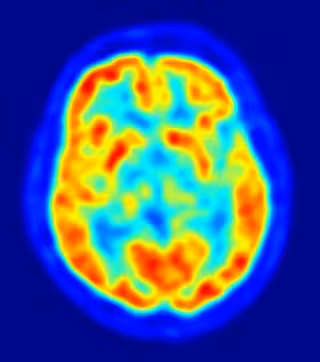

Investigadores del Consejo Superior de Investigaciones Científicas (CSIC) ha demostrado que las colisiones al azar entre las neuronas durante el desarrollo del cerebro crean patrones ordenados cuando no existen señales que guíen su destino, lo que podría explicar las diferencias cerebrales entre los individuos de una especie.

La investigación, publicada en la revista 'Neuron', ha descubierto que es el contacto al azar y la posterior repulsión entre las neuronas que entran en contacto entre sí lo que determina su distribución en la superficie de la corteza cerebral.

Concretamente, el hallazgo muestran que el movimiento de las células de Cajal-Retzius, un tipo de neuronas que se generan muy temprano en el cerebro embrionario y que juegan un papel clave en el desarrollo de la corteza cerebral, no está dirigido por señales guía que les indiquen su punto de destino.

La corteza cerebral es una de las regiones más complejas del cerebro de los mamíferos y alcanza su máximo desarrollo en humanos y otros primates. Para que se forme correctamente hacen falta multitud de señales químicas que dirigirán a las células que lo componen hacia la posición que finalmente van a ocupar y que determinarán la función que van a desempeñar.

A partir de estas interacciones al azar entre las células en migración surgen siempre distribuciones muy similares, aunque no idénticas. "Puesto que estas neuronas corticales son las que definen posteriormente las diferentes habilidades de cada tipo de corteza (visual, motora, etc.), es muy probable que la variabilidad que emerge durante el desarrollo tenga mucho que ver con las diferencias entre unas personas y otras", añade Marín.

Los investigadores recuerdan que la colocación de las células de Cajal-Retzius parece ser fundamental para que las neuronas de la corteza cerebral se distribuyan en matrices ordenadas que forman capas horizontales y columnas verticales. Esta organización es crucial para que las áreas funcionales de la corteza cerebral, que son poblaciones de neuronas especializadas en procesar información de determinada modalidad sensorial (como la vista o el tacto) o motora, puedan interpretarla de forma eficaz.